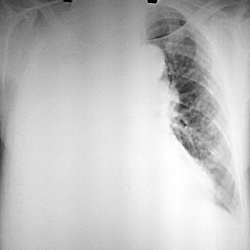

Поступила с одышкой, немощностью, на сидячей каталке. Болеет долго, тянули, всё думали, думали, в итоге года через 2 пришли к врачам. На УЗИ - метастазы в печени. В легких - вот это (при поступлении...